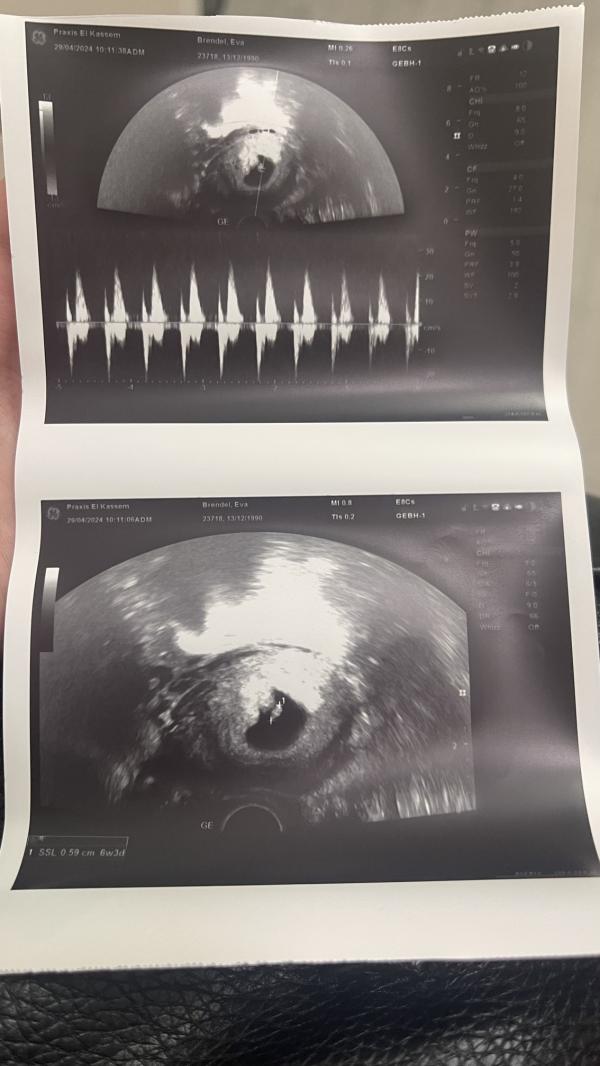

29.04 в 6.3 Wo. мы были у врача

Нас поставили на учет с фисташкой 🥰

Слушала сердечко

И прогестан 100, 1 утром и вечером